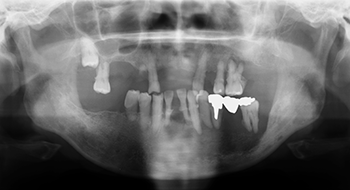

図❷ 初診時のパノラマX線写真

パノラマX線画像所見:57は浮遊しており、その周囲骨は比較的辺縁明瞭であるが、一部虫食い状を呈する高度な骨吸収像を認めた(図❷)